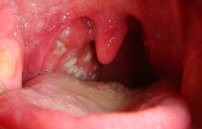

Гной – это своеобразная реакция организма на активное размножение патогенных микробов. Если появился гной в горле, то виной этому возникновение и развитие бактериальных заболеваний.

При помощи гноя организм старается справиться с инфекцией и очистится от стафилококков и стрептококков.

Некоторые недуги верхних дыхательных путей провоцируют скопление экссудата на задней стенке горла.

Ввиду отсутствия полноценного оттока воспалительный процесс распространяется на расположенные рядом ткани. Поэтому важно убрать воспаление как можно скорее.

- гнойные заболевания горла (ангина, абсцесс, аденоидит, гнойный фарингит, ларингит, тонзиллит).